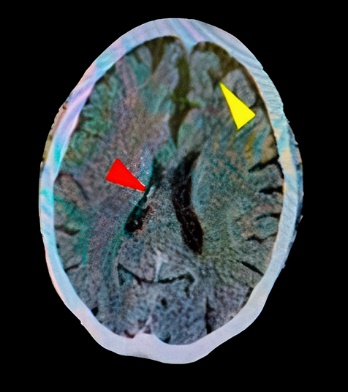

Mujer de 76 años procedente de Trujillo, usuaria de marcapasos desde hace 5 años por bradiarritmia, con antecedentes de hipotiroidismo controlado, HTA no controlada y múltiples intervenciones quirúrgicas. No refiere alergia a medicamentos. Ingresa a emergencia por presentar desde hace 30 minutos trastorno de conciencia, dificultad para la marcha y disartria. Al ingreso se registró PA: 173/118 mmHg, FC: 128 lpm, FR: 28 rpm, ECG: 11 puntos. Peso: 90 kg Talla: 160 cm. Presenta somnolencia y hemiplejia izquierda con parálisis facial central izquierda. Se solicitó TEM cerebral sin contraste, el cual reveló foco isquémico a nivel parietal derecho (figura 1). Se estableció como diagnóstico ECV isquémico. A las 2 horas, presentó PA: 183/72 mmHg, FC: 128 lpm, FR: 28 rpm, ECG: 13 puntos. Se optó por tratamiento trombolítico con Alteplasa 70 mg E.V. (10 mg en 5 minutos seguido de 60 mg en 60 minutos).

Se evidencia infarto en territorio de la ACM derecha. Calcificaciones a nivel de ambos ganglios basales con arterias vertebrales calcificadas (cabeza flecha roja), cambios tróficos a nivel del parénquima cerebral (cabeza flecha amarillo).